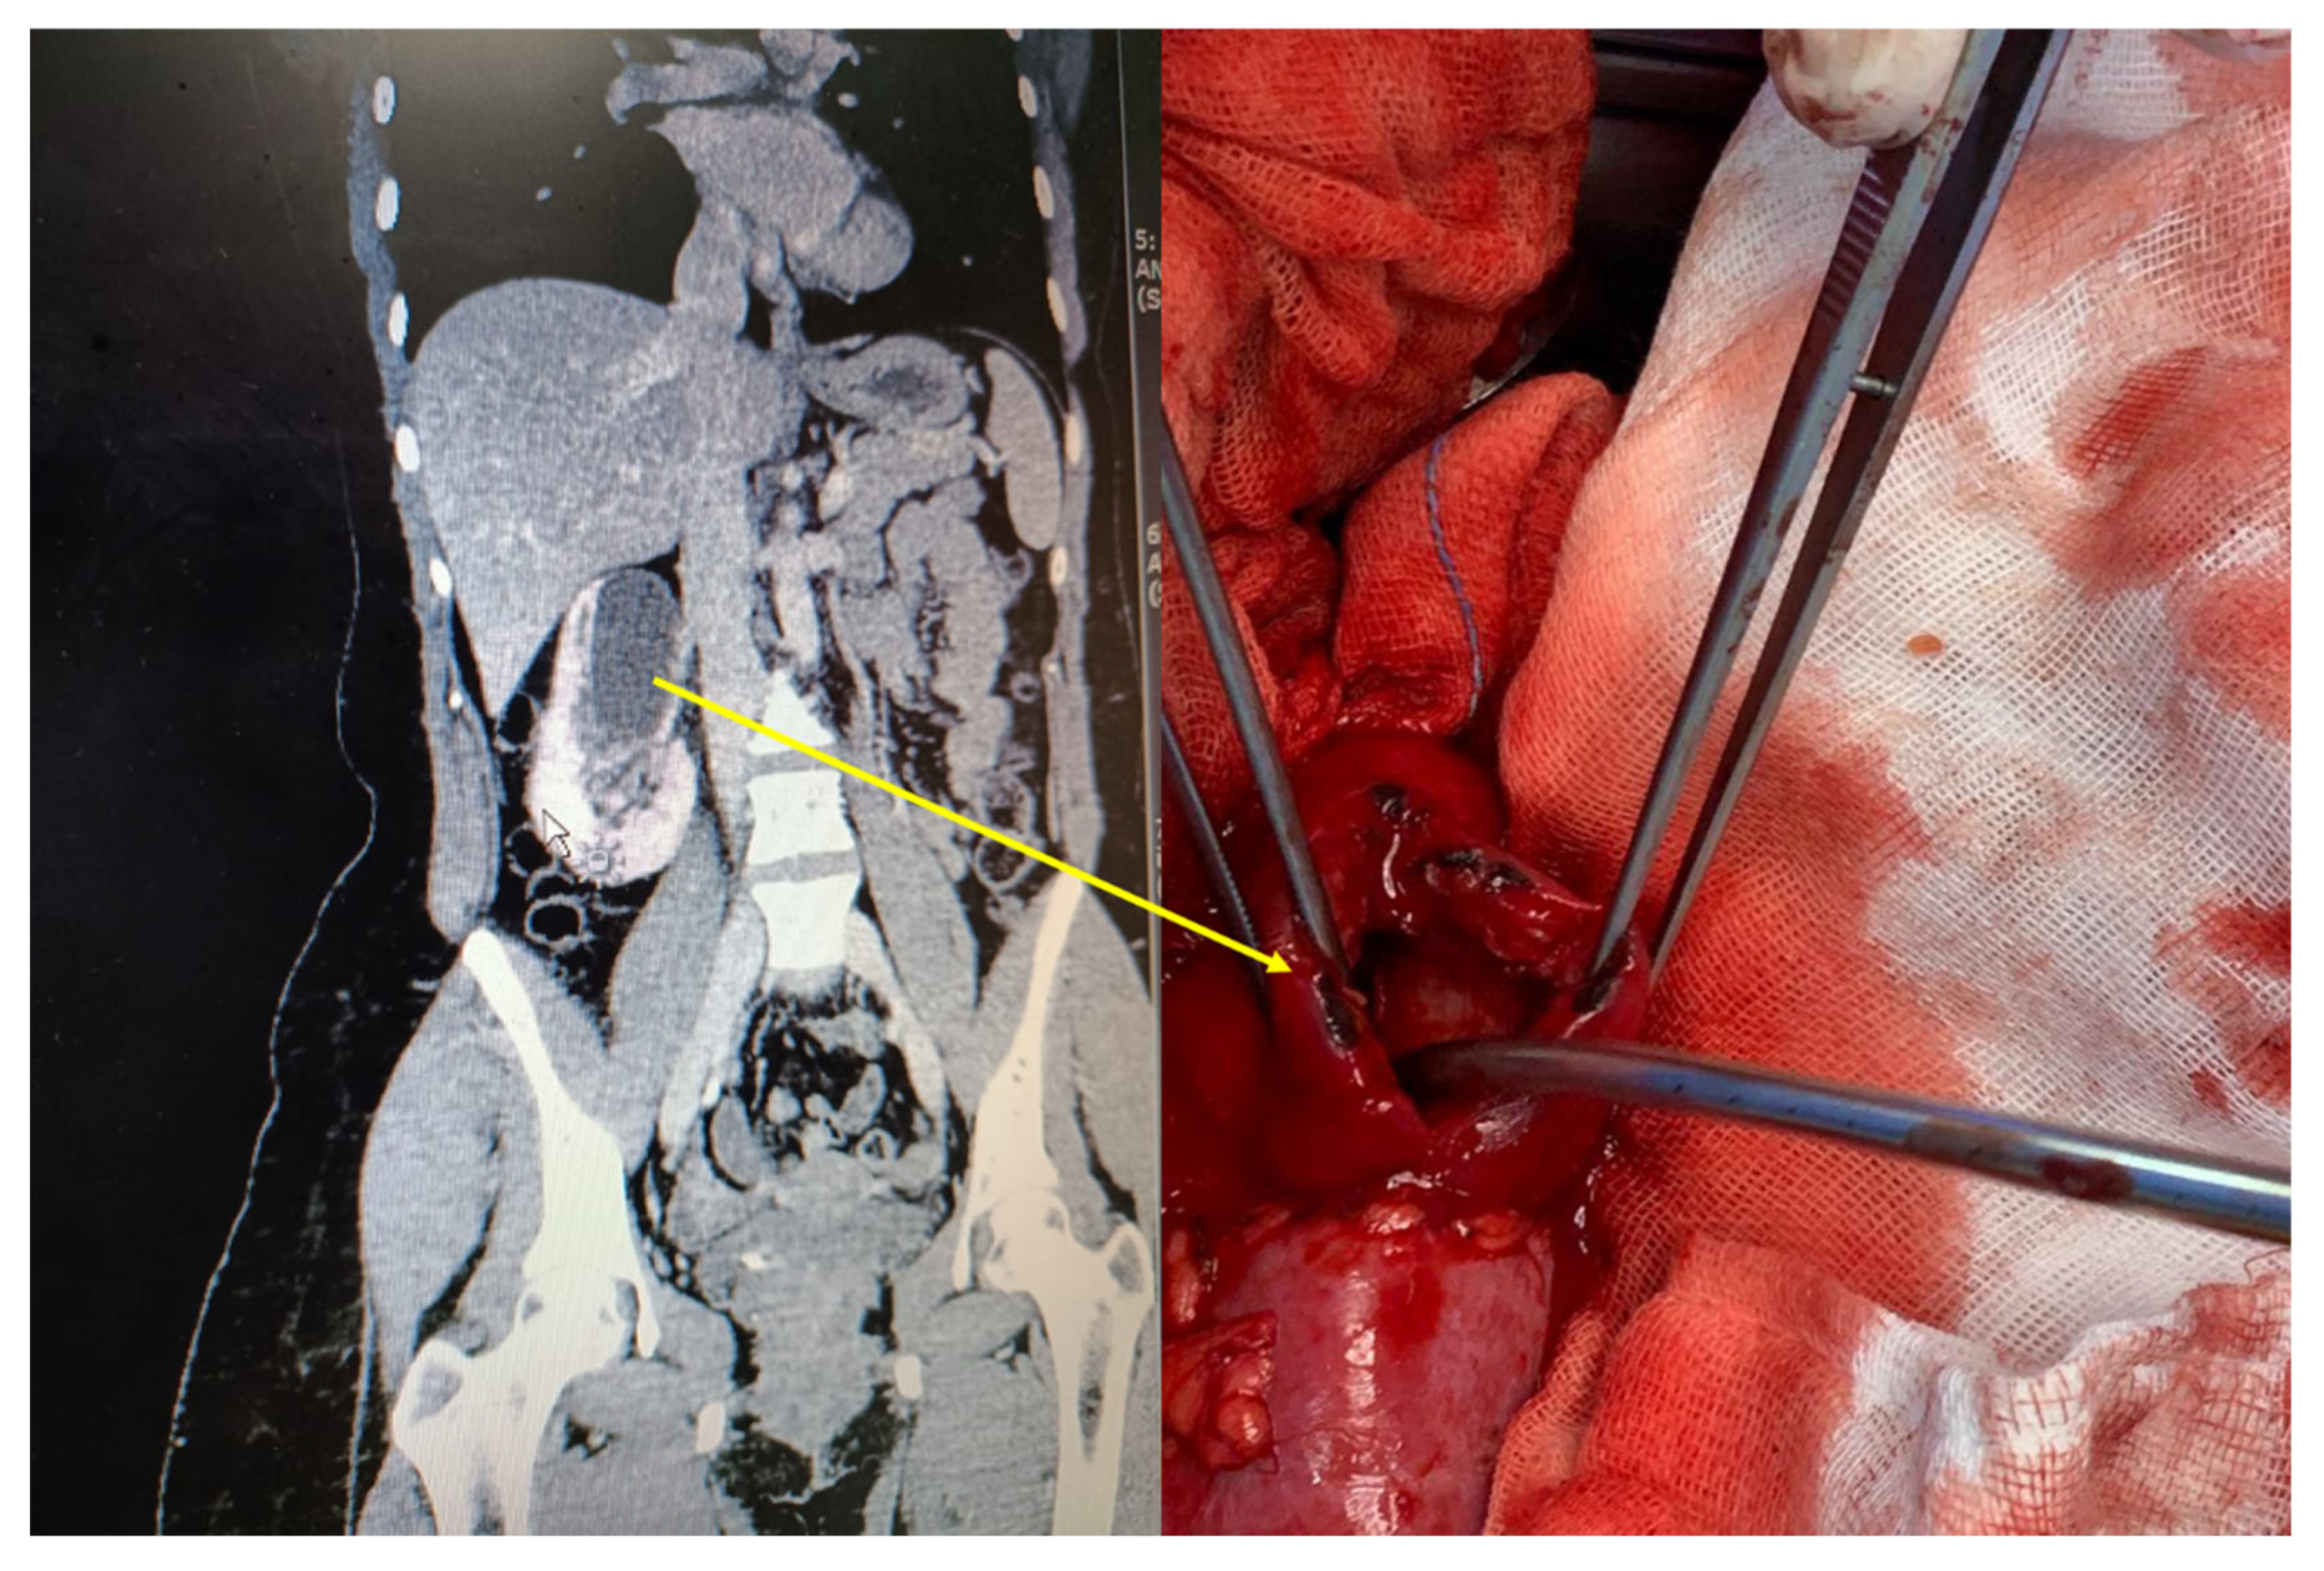

- Fadel, M.G.; Carey, M.; Bolgeri, M. Infected and obstructed kidney secondary to sloughed necrotic renal papilla. Case Rep. 2018, 2018, bcr–2018–227403. [Google Scholar] [CrossRef]

- Rao, V.C.; Bhat, S.S.; Vijayan, P.; Ramamurthy, S. Endoscopic intervention in obstructive renal papillary necrosis. Indian J. Urol. 2004, 20, 29. [Google Scholar]

- Pan, H.H.; Luo, Y.J.; Zhu, Q.G.; Ye, L.F. Renal papillary necrosis with urinary tract obstruction: A case report. World J. Clin. Cases 2022, 10, 5400–5405. [Google Scholar] [CrossRef]